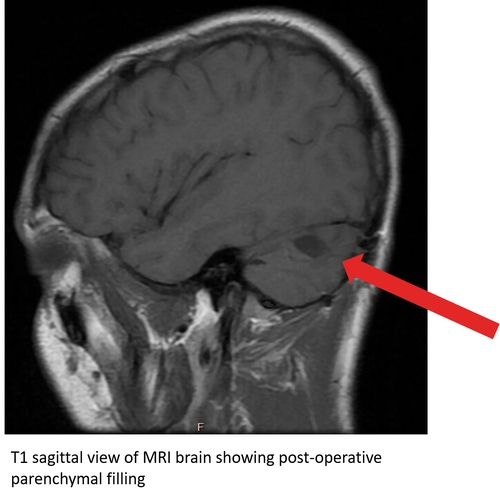

At the time of discharge, he was ambulating without assistance, though with some subjective dizziness. He began balance training at 2 weeks post-op and was able to return to light aerobics and weight training by 4 weeks. A repeat MRI at 6 weeks revealed no residual tumor along with appropriate parenchymal filling of the cerebellar defect. Case Photo #3 Case Photo #4 He was able to progress his aerobic activity at 8 weeks. He received full clearance to return to practice and full weight training at 12 weeks. By 16 weeks, he had a full return to sport. A repeat MRI performed 6 months post-op revealed further parenchymal filling of the defect and no new masses.